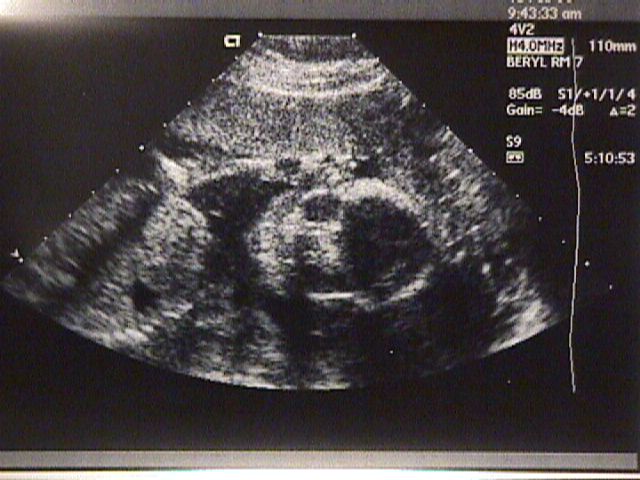

20 weeks, about 15cm.